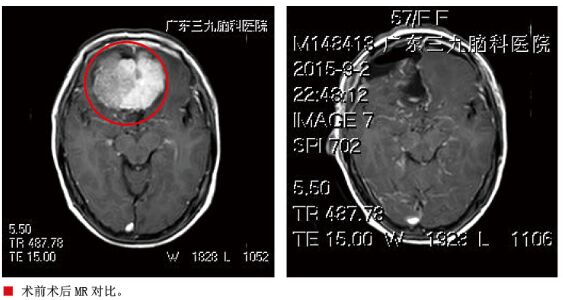

入院后完善相关检查及术前准备, 8月31日在全麻下为患者行“经右额前纵裂前颅底巨大脑膜瘤切除术”,术中取额部冠状切口,取右额部直径约5cm骨瓣,前至眶上,内侧至中线,轻掰额叶脑组织,即见白色肿瘤组织,质中,肿瘤基底部位于蝶骨平台、嗅沟区域,从前颅窝底逐步烧灼分离肿瘤基底部,显微镜下分块切除肿瘤,术中见视交叉被肿瘤压迫移向下方、颈内动脉及其分支受肿瘤压迫向后移位,大脑前动脉分支被肿瘤包绕,经仔细分离,视神经及颈内动脉分支均保护完好,肿瘤最终镜下全切,术中出血约600ml,输红细胞2单位。患者术后视力、视野较前有所改善,肢体活动良好,病情稳定后出院。病理结果示“过渡型脑膜瘤(WHO1级)”。

脑膜瘤,通常为生长缓慢,边界清楚(非侵袭性)的良性病变。过渡型脑膜瘤是界于内皮型和纤维型之间的一种脑膜瘤,其肿瘤细胞呈纺锤体形,部分区域可见典型的脑脊膜瘤细胞,并呈旋涡状排列,可有钙化(沙样瘤小体)。蝶骨平台脑膜瘤最先影响嗅神经,患者往往以嗅觉障碍为首发症状,随着肿瘤的增大逐渐出现头痛、头晕的症状。治疗主要以手术为主,对于手术切除不干净的肿瘤术后辅以放疗。本例患者,肿瘤体积大,基底部位于蝶骨平台,往后压迫视交叉,包绕并向后外侧挤压双侧颈内动脉,手术中如何保护颈内动脉及其分支,减少对垂体柄、视神经、下丘脑等重要结构的损伤成为手术的难点。手术过程中先处理肿瘤基底部,有效的减少了术中出血,经小心分离,成功保护颈内动脉及其分支,减少对垂体柄、视神经、下丘脑等重要结构的损伤,患者术后恢复良好,效果满意。